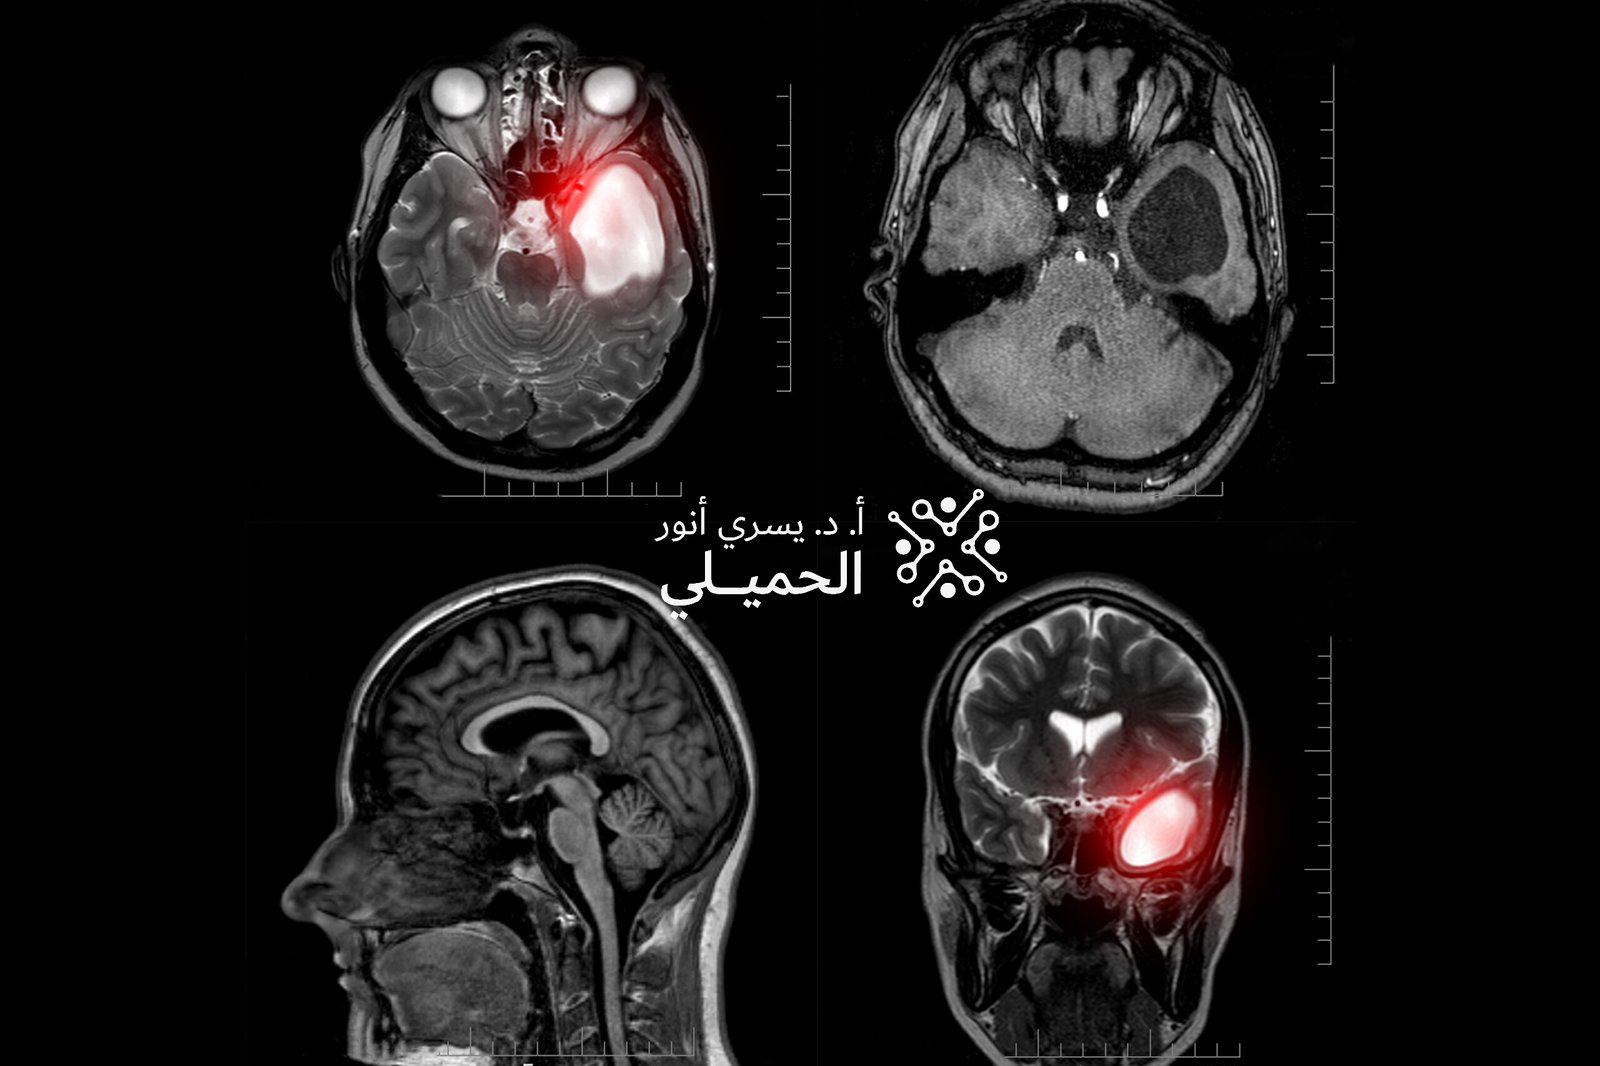

نزيف المخ: أسبابه، أعراضه، طرق التشخيص والعلاج الشامل

يُعد نزيف المخ أحد أخطر الحالات العصبية الطارئة التي تستوجب تدخلاً طبيًا سريعًا، نظرًا لتأثيره المباشر على خلايا الدماغ ووظائف الجسم الحيوية. يحدث النزيف عندما يتسرب الدم خارج الأوعية الدموية

اعراض ورم الدماغ الحميد

اعراض ورم الدماغ الحميد قد تختلف حسب حجم الورم وموقعه داخل الدماغ، لكنها غالبًا ما تتطور ببطء وتظهر بشكل تدريجي، وقد تشمل اعراض ورم الدماغ الحميد الصداع المستمر، والدوخة، واضطرابات

ما هى اعراض اورام المخ؟

ما هى اعراض اورام المخ؟ هذا السؤال يُعد من أكثر الأسئلة التي تشغل بال من يعانون من مشكلات عصبية غير مفسرة أو تغيرات مفاجئة في القدرات الجسدية أو الذهنية. فعلى